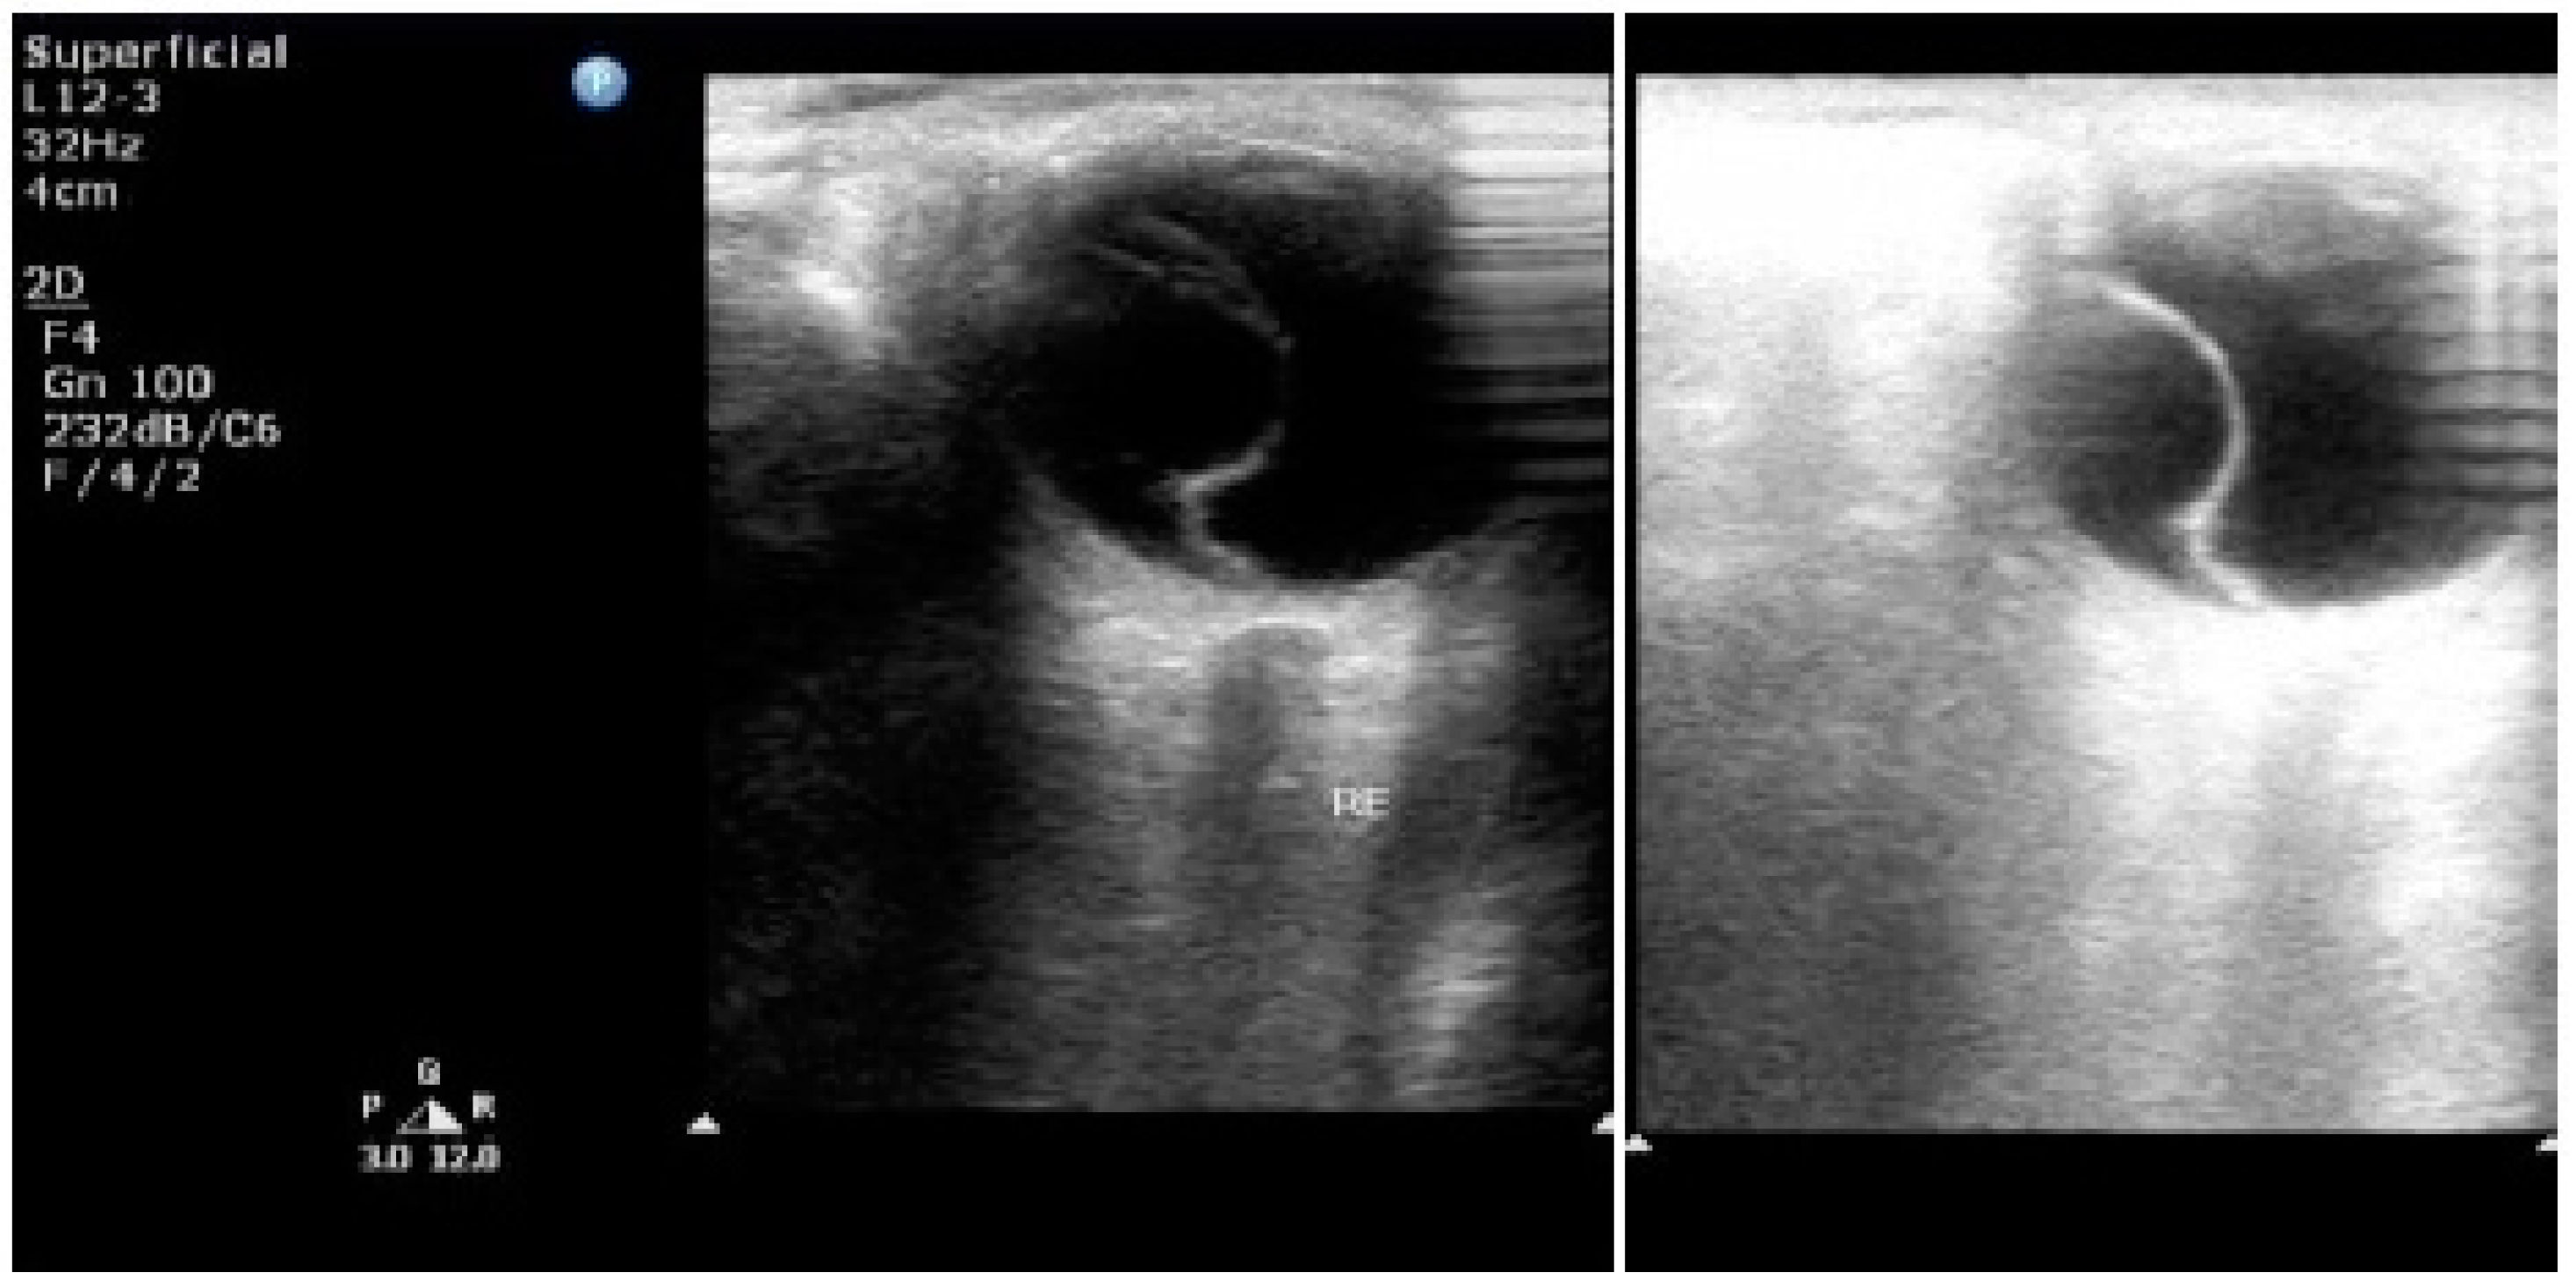

7. Ultrasonography

- Fledelius, H.C. Ultrasound in ophthalmology. Ultrasound Med. Biol. 1997, 23, 365–375. [Google Scholar] [CrossRef]

- Sconfienza, L.M.; Lacelli, F.; Ardemagni, A.; Perrone, N.; Bertolotto, M.; Padolecchia, R.; Serafini, G. High-resolution, 3-D, and contrast-enhanced ultrasonographic findings in diseases of the eye. J. Ultrasound 2010, 13, 143–149. [Google Scholar] [CrossRef] [PubMed]